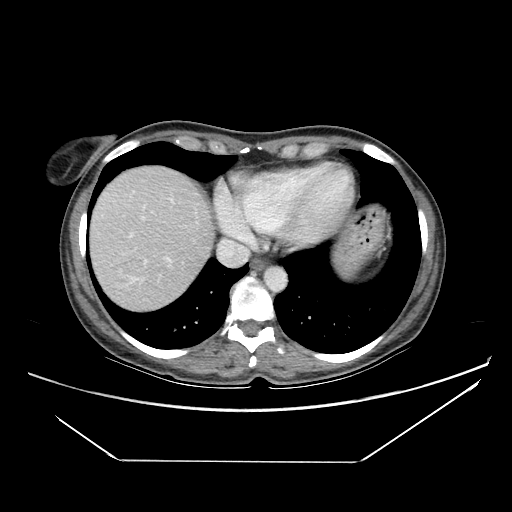

Image Grid

4Γ—3 grid: Rows show different image types (Original NATIVE, Reconstructed NATIVE, Original VENOUS, Generated VENOUS), Columns show windowing techniques (No Window, Lung Window, Mediastinum Window)

Original VENOUS CT scan

Full window (WL 1023.5, WW 4095 β†’ Low βˆ’1024, High +3071)

Actual HU range: [-160.0, 240.0]

Lung window (WL -600, WW 1500 β†’ Low βˆ’1350, High +150)

Actual HU range: [-160.0, 150.0]

Mediastinum window (WL 40, WW 400 β†’ Low βˆ’160, High +240)